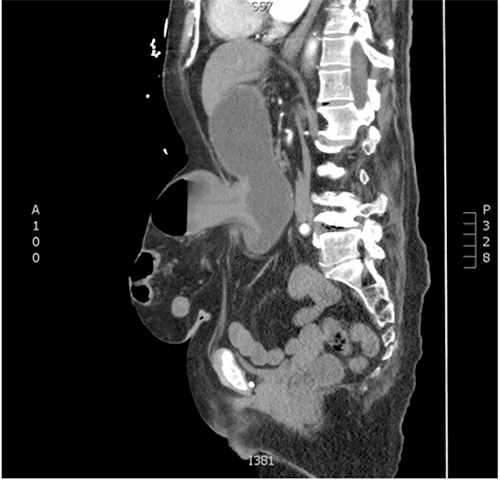

She underwent hematological and biochemical investigations as well as further imaging in the emergency department. Her hematological investigations revealed an elevated white cell count at 12.20 × 109/L. Her biochemical investigations showed an elevated C-reactive protein at 310, alkalosis with a pH of 7.49, hypernatremia, hypokalaemia, and an elevated creatinine of 264. She was in hypochloraemic, hypokalaemic metabolic alkalosis which is characteristic of a gastric outlet obstruction. Her CT abdomen and pelvis scan with intravenous contrast demonstrated a large umbilical hernia containing the pylorus and a loop of transverse colon. The radiological fascial defect was 5.2 × 5.9 cm.

Figure 1. CT Scan Showing Large Ventral Hernia Containing Pylorus and Bowel. Published with Permission